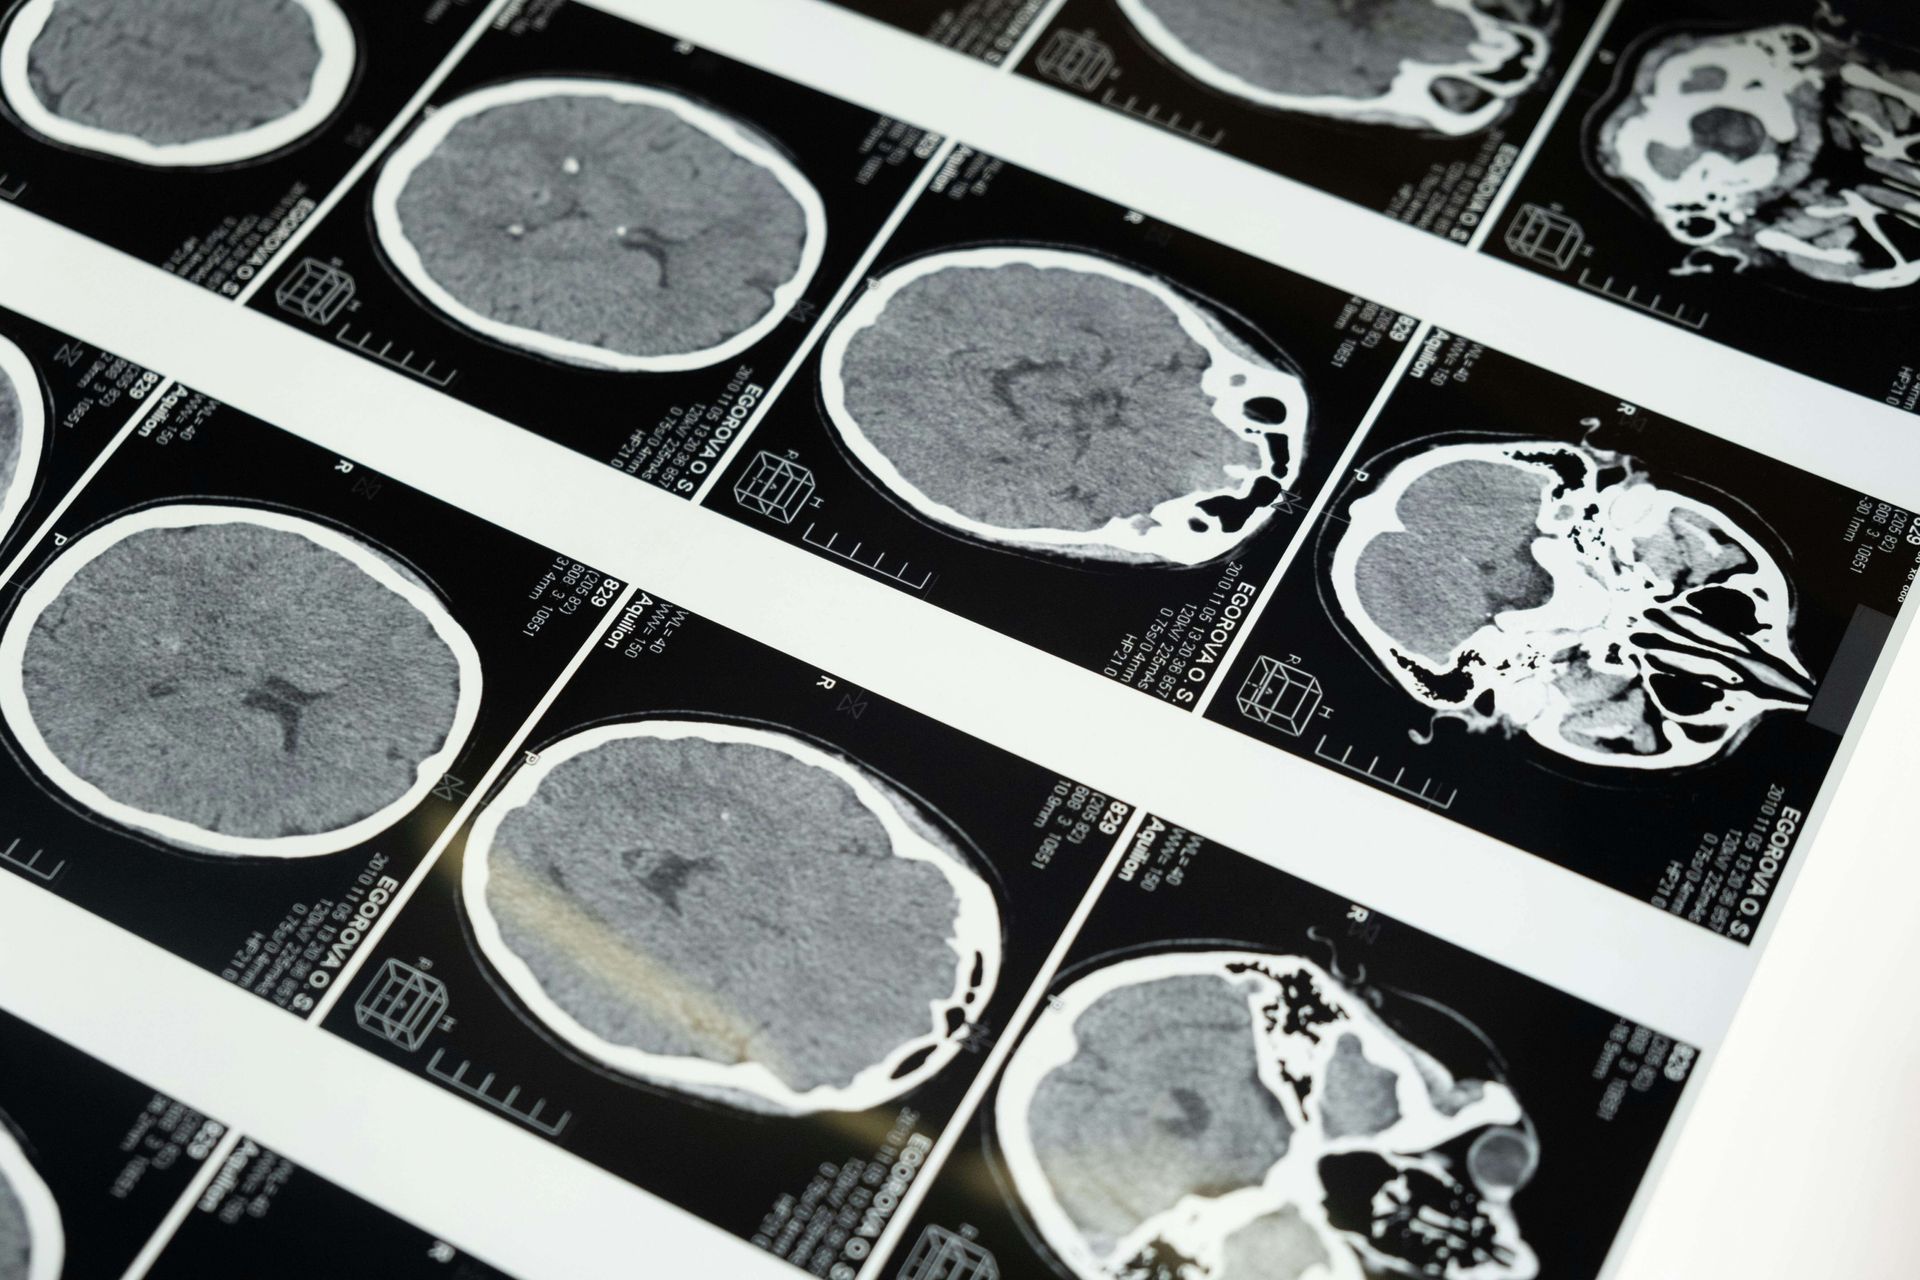

Research led by Dr. Nora Volkow and colleagues suggests that addiction profoundly alters the functional architecture of the brain's reward circuit. These findings are summarised in a review article published by Volkow et al in The Journal of clinical investigation: “The addicted human brain: insights from imaging studies”. Utilizing functional MRI (fMRI) studies, has been pivotal in demonstrating how addiction leads to these neurobiological changes. One significant finding is the key role played by the prefrontal cortex, a region critical for decision-making, impulse control, and self-regulation. Functional imaging studies have shown that during drug intoxication, or during craving, these frontal regions become activated as part of a complex pattern that includes brain circuits involved with reward (nucleus accumbens), motivation (orbitofrontal cortex), memory (amygdala and hippocampus), and cognitive control (prefrontal cortex and cingulate gyrus). Volkow's research highlights that this dysregulation in the reward circuit is not just a matter of one region but involves the complex interplay between various parts of the brain. For instance, while there's reduced activity in the prefrontal cortex, there's often enhanced activity in areas of the brain associated with emotional processing and memory, which can trigger strong cravings when exposed to cues associated with the addictive substance or behaviour.